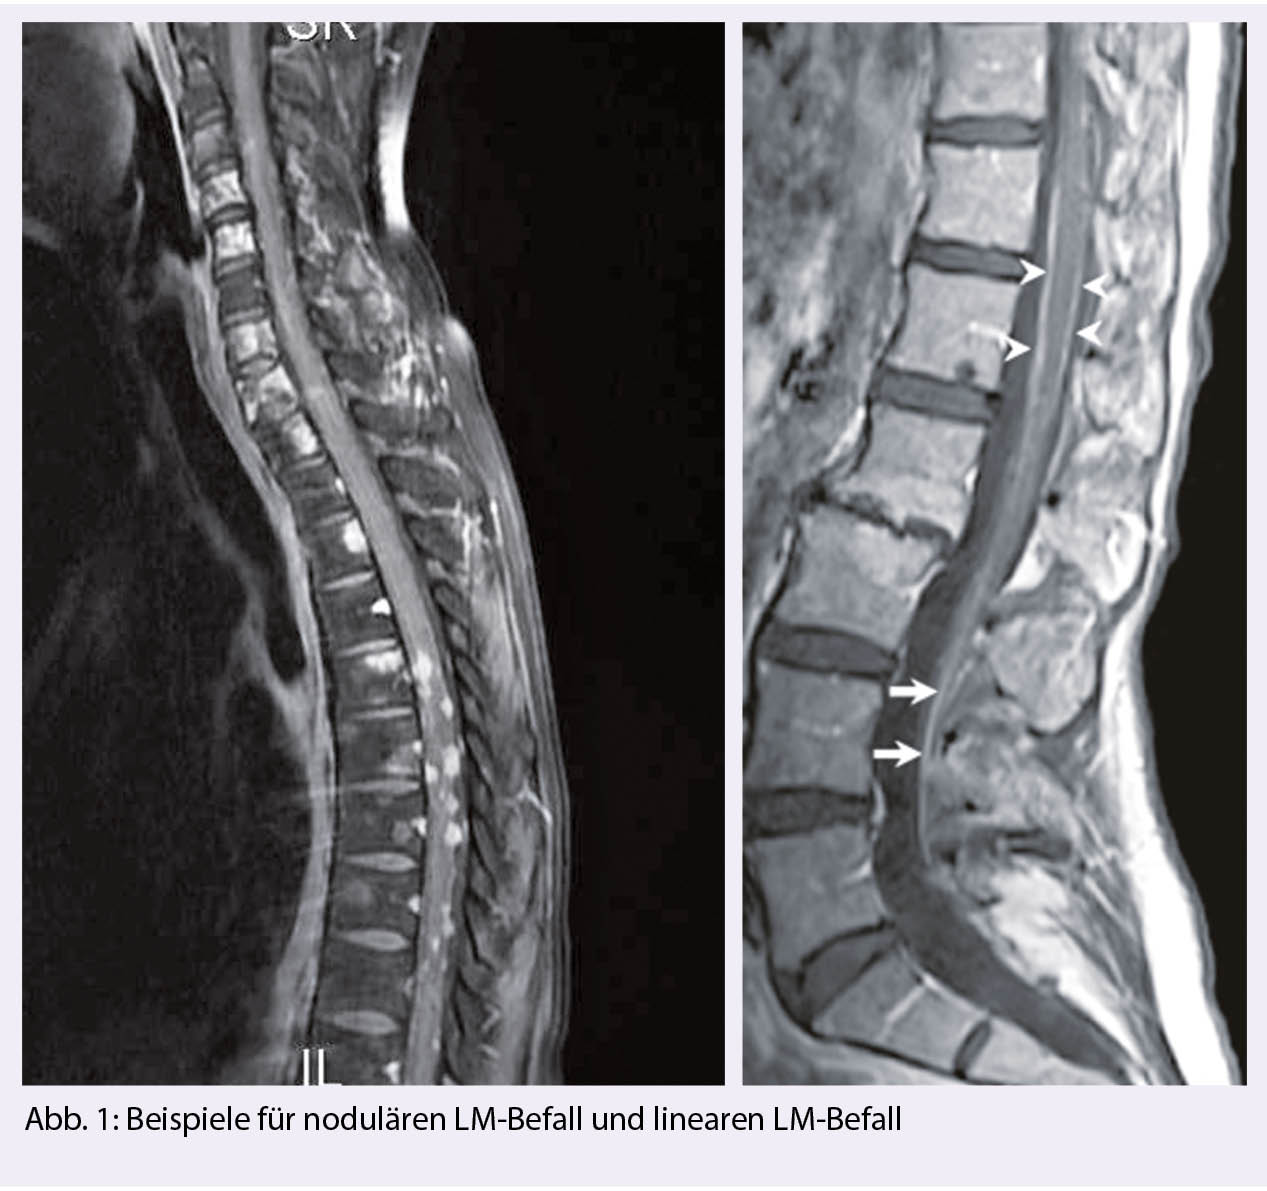

Man unterscheidet einen nodulären Tumorbefall, an den Meningen adhärent, eine tapetenartige Auskleidung der Meningen und frei flottierende Tumorzellen oder eine Kombination dieser Manifestationen (Abb. 1). Es ist nachvollziehbar, dass bei der nodulären, adhärenten Form, keine Tumorzellen im Liquor fassbar sein können.

Aus den verschiedenen Befallsarten ergeben sich therapeutische Konsequenzen. Bei ausgedehntem nodulären Befall bietet sich eine lokale Radiotherapie an, besonders, wenn die Liquorzirkulation gefährdet ist, Symptome vorliegen oder ein Hydrocephalus droht, wohingegen 1-2 mm schmale «Tapeten» oder frei zirkulierende Tumorzellen einer intrathekalen Therapie besser zugänglich sind. Ohne Therapie verläuft das leptomeningeale Wachstum innert weniger Wochen tödlich. Mit konventioneller Systemtherapie liegt das mediane Überleben bei etwa 3-6 Monaten. Zielgerichtete Therapien können langanhaltende Tumorkontrollen erreichen, besonders bei HER-2-positiven, EGFRmut und ALK- alterierten Tumorentitäten (1).